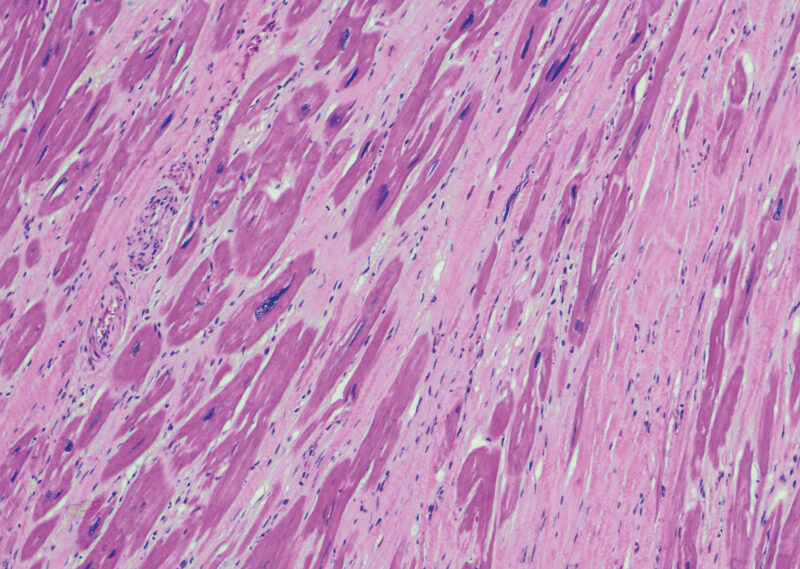

Gezielte medikamentöse Behandlung möglich

Bei hypertrophen Kardiomyopathien kommt es zu einer Herzmuskelverdickung ohne begleitende Dilatation. In 70% der Fälle liegt eine Obstruktion des linksventrikulären Ausflusstraktes vor, man spricht dann von einer hypertroph-obstruktiven Kardiomyopathie (HOCM)....…